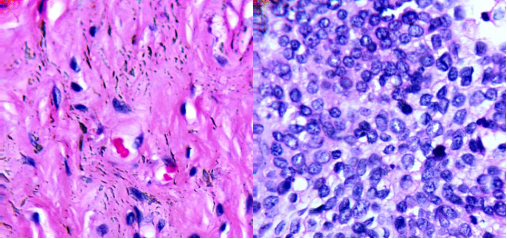

(a)100X宮頸癌非腫瘤切片;(b)100X宮頸癌腫瘤切片

(a)40×膀胱癌非腫瘤切片;(b)40×膀胱癌腫瘤切片

醫用顯微成像光譜儀數據